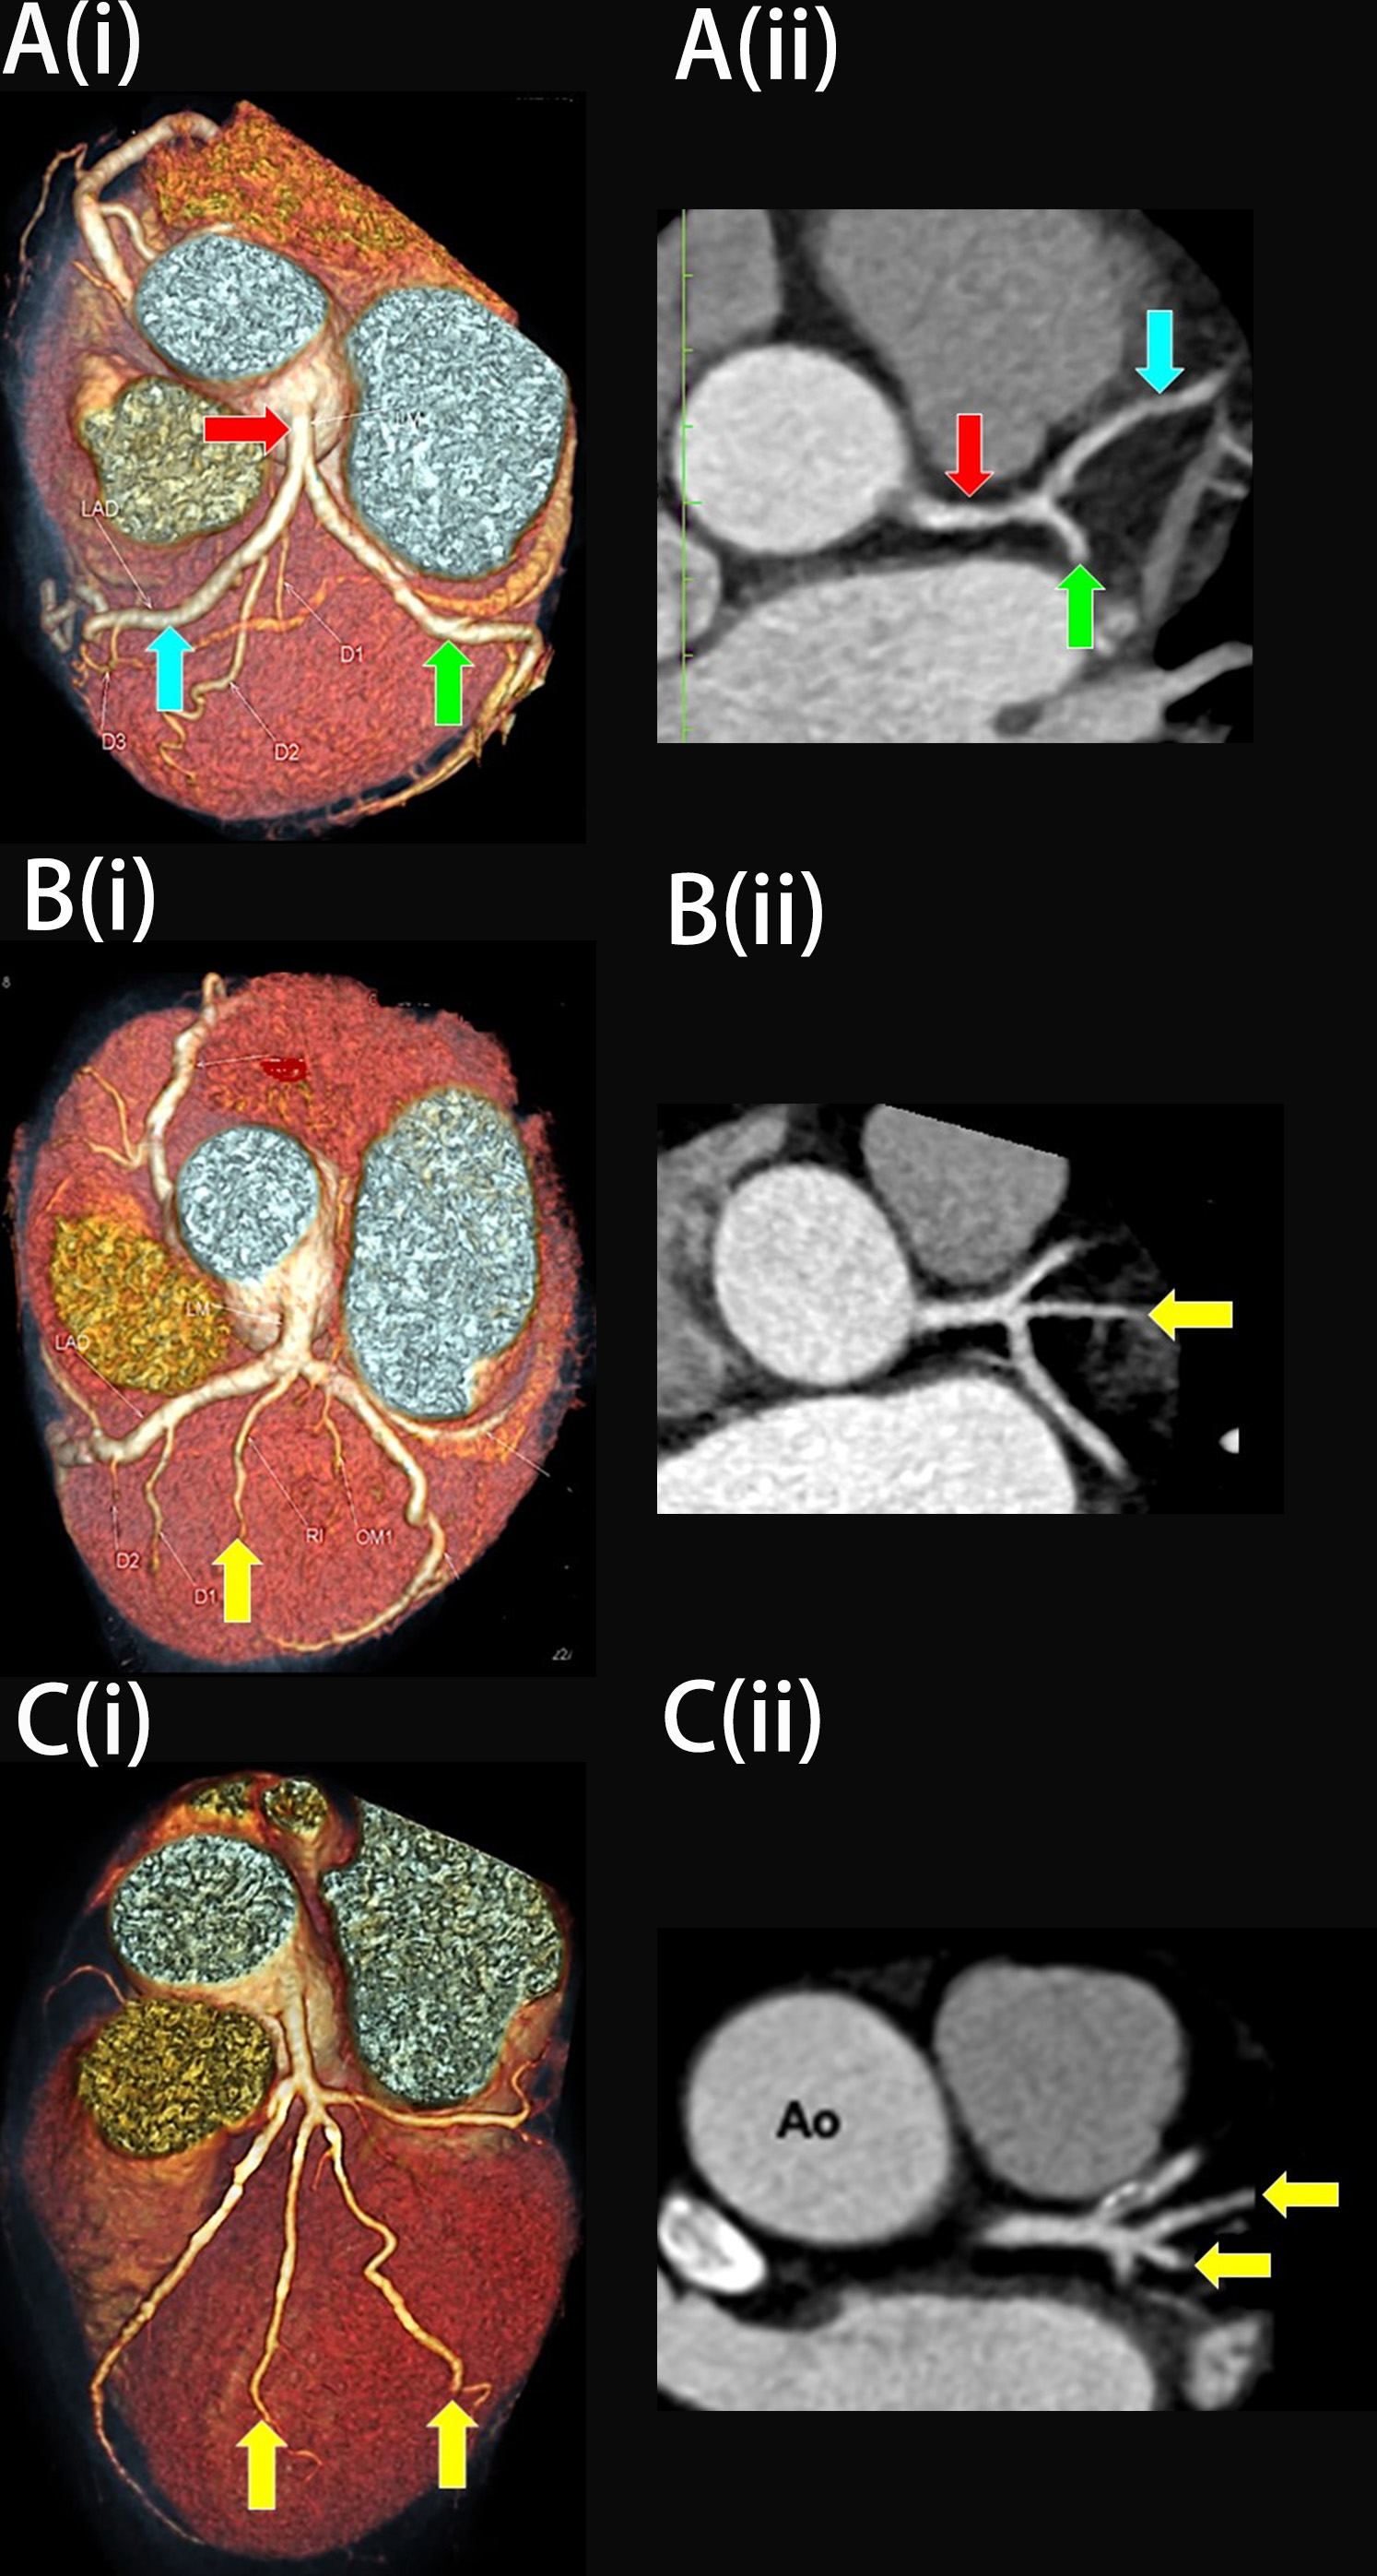

Fig. 6. Plaque deposition at the left bifurcation region in multiplanar reconstruction (MPR). (A) Plaque deposition at the distal portion of the left main coronary artery (LMCA) in the presence of ramus intermedius (RI) (axial view). (B) Plaque deposition at both proximal and distal portions of LMCA (coronal view). (C) Plaques at the lateral wall of proximal left anterior descending (pLAD) and proximal left circumflex (pLCx) arteries near their ostia in the presence of RI (axial view). The red arrow indicates LMCA, the blue arrow indicates pLAD, the green arrow indicates pLCx, and the yellow arrow indicates RI.

Table 1 highlights the distribution of plaques and their association with the RI. Analysis of the plaque at the LMCA, pLAD and pLCx was done using MPR images by two investigators with inter-rater kappa of 0.9 for LMCA, 0.7 for pLAD, and 0.8 for pLCx, respectively. There were 26 patients with plaques located at the LMCA; most of these were located at the distal portion (11.5%, n = 16), followed by both proximal and distal portions (6.5%, n = 9) and at the proximal (0.7%, n = 1) portion of the artery. Analysis showed that the RI had no significant relation to plaque development in these arterial portions individually, but concurrently influenced plaque development in both proximal and distal portions as shown in Fig. 6A,B. Multivariate analysis revealed that the RI posed an eight-fold increased risk for plaque deposition at both portions of the LMCA compared to patients without an RI (14.9%, n = 7, adjusted ratio (aOR) = 8.5, 95% confidence interval (CI) = 1.7, 43.0, p = 0.01, Table 1, LMCA).

There were 44 patients who had plaques within the 10 mm distance from the ostium of pLAD. Most of the plaques were formed along the lateral wall of this artery (17.3%, n = 24), followed by plaques along both lateral and medial walls (12.9%, n = 18) and plaques along the medial wall only (1.4%, n = 2). The presence of the RI tripled the risk for plaque deposition along the lateral wall in pLAD (27.7%, n = 13, aOR = 3.5, 95% CI = 1.1, 11.3, p = 0.036) and added a four-fold increased risk for plaque formation involving both lateral and medial walls of this artery (23.4%, n = 11, aOR = 4.3, 95% CI = 2.1, 17.4, p = 0.038; Table 1, pLAD). Fig. 6C demonstrated a plaque at the lateral wall of pLAD.

There were 27 patients with plaque deposition within the 10 mm distance from the ostium of the pLCx (Fig. 6C), but the bivariate analysis did not show that the RI had any association with plaque deposition at any of the walls of this artery (Table 1, pLCx). In addition, 14.9% (n = 7) of patients with an RI were noted to have plaque deposition in the pLCx (Table 1, pLCx and Fig. 6C). Out of 47 patients that had an RI, 14 (30.0%) demonstrated stenotic plaques in their RI (Table 1, RI and Fig. 6C). Fig. 6C demonstrated a plaque involving the RI.